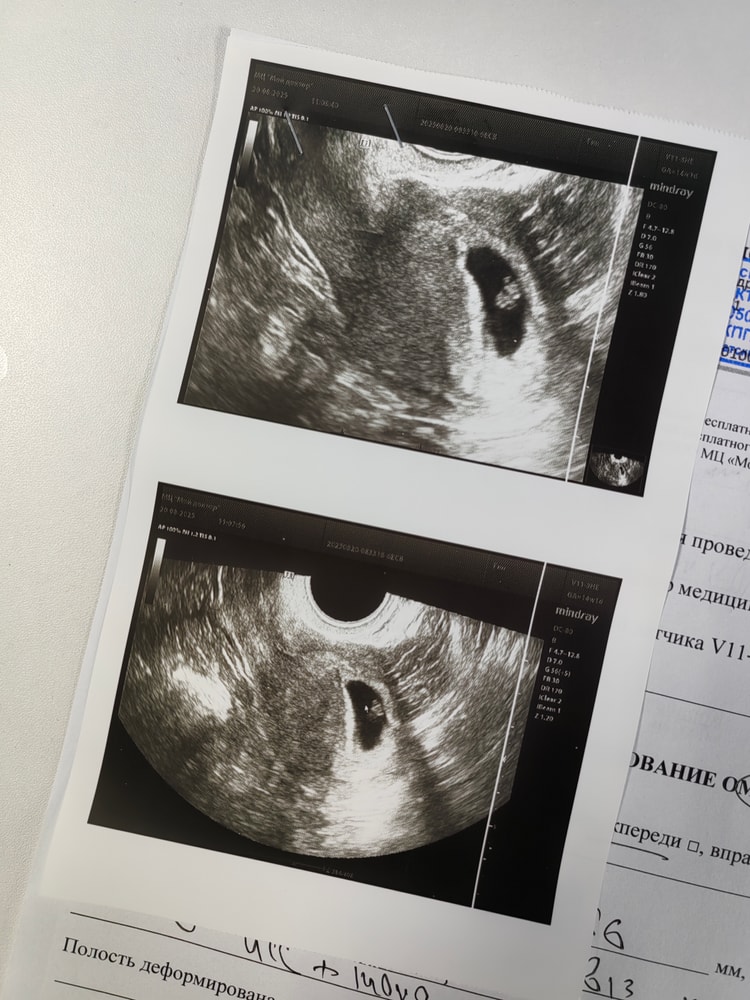

Сегодня сходила на повторное узи, акушерский срок 7н 1д.

Нашли эмбриончик с сердцебиением 🥰 140 ударов в минуту. Ктр 4,8 мм. Желточный мешочек 4 мм.

Соответствует 6-7 неделям